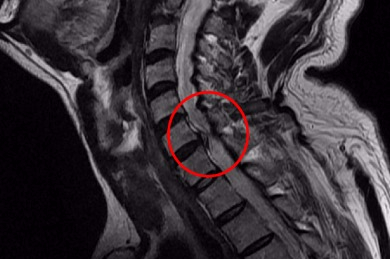

목 뼈와 뼈 사이의 디스크가 제자리에서 이탈되어 신경을 압박한 경우 혹은 뼈 조직이 비정상적으로 자라 목을 지나는 척추 신경이 눌려 통증을 인지하는 질환이예요.

목 디스크 증상은 어깨, 목 손목등 근육에 통증을 위시하여 인지를 할 수 있어요. 초기에는 하루종일 근육이 뻐근한 경우 혹은 찌릿찌릿한 통증이 동반된다 하였습니다. 만에 하나라도 경추 가운데 통증을 느끼시는 분들 중에는 과도한 경우 하반신 마비까지 올 수 있기 때문에 조기치료가 필수입니다.

통증이 팔, 어깨, 팔에서 손 및 손가락 등으로 뻗치게 되었는데 이때 신경 분포에 따라서 대부분 5번 신경이 눌리면서 어깨가 아프고, 6번 신경이 눌리게 된다고 합니다. 또한 어깨에서부터 팔을 지나 엄지손가락까지 저리고 아프게 되면서 7번과 8번 신경이 눌려지게 되어 손과 손가락 마디마디가 저리고 아프게 되기도 합니다.

디스크의 수핵이 빠져나가거나 퇴행성 경추 척추증 및 경추관협착증 등으로 척수가 눌리게 되면 대다수는 팔의 힘이 빠지는 느낌을 받을 수 있습니다.